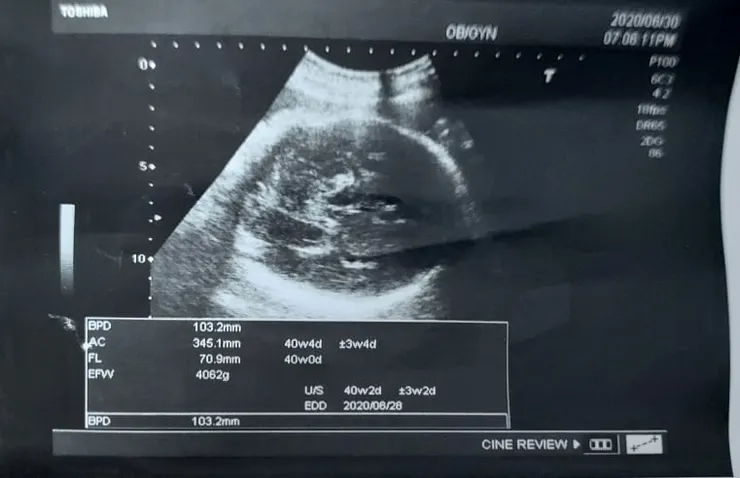

2020.6.30 (38W4062)

今天去產檢醫生說因為寶寶頭大,算起來比較重,目前已經突破4000,但是如果我165好像勉強可以試試看,真的到時候開指生不出來,就只能剖腹,所以我決定現在來吃個麻辣泡麵,明天再來個麻辣鍋,網路上說吃麻辣的很容易促進收縮喔,還有冰棒,希望本週可以出生,但是本週才38,上次醫生說39機率大,喔天啊,再擺下去不就五仟了。

2020.7.01(三)AM8:30 (7.739W--4075G)

天啊,已經七月了欸,我還一直感覺是六月 我的280天APP已經到個位數了,超級感謝大家對我的關心,昨天晚上還有天使和我分享,有關超音波小孩太大的問題 結果剖腹出來也沒真的破四千,似乎多一點繼續抗戰的動力了, 不然昨天聽完醫生的檢查,差點要放棄了,想說算了,隨便吃好了,反正這麼大 都生不出來了,雖然我的醫生一直鼓勵我可以自然試試看,很溫柔的說對媽媽沒有風險,假設第二產程真的不順利,馬上剖腹都可以,而且他說我算高應該有機會可以嘗試, 只是我超級怕來個全餐,他說通常出不出的來他也不會勉強,看當下就會知道有沒有卡住,到時候他會評估真的覺得不行,我們就開刀,我們大家一起看下去,看看這趟信德之路怎麼發展, 我真的是小信德的人,但是我常常練習我的信德,天主請幫助我